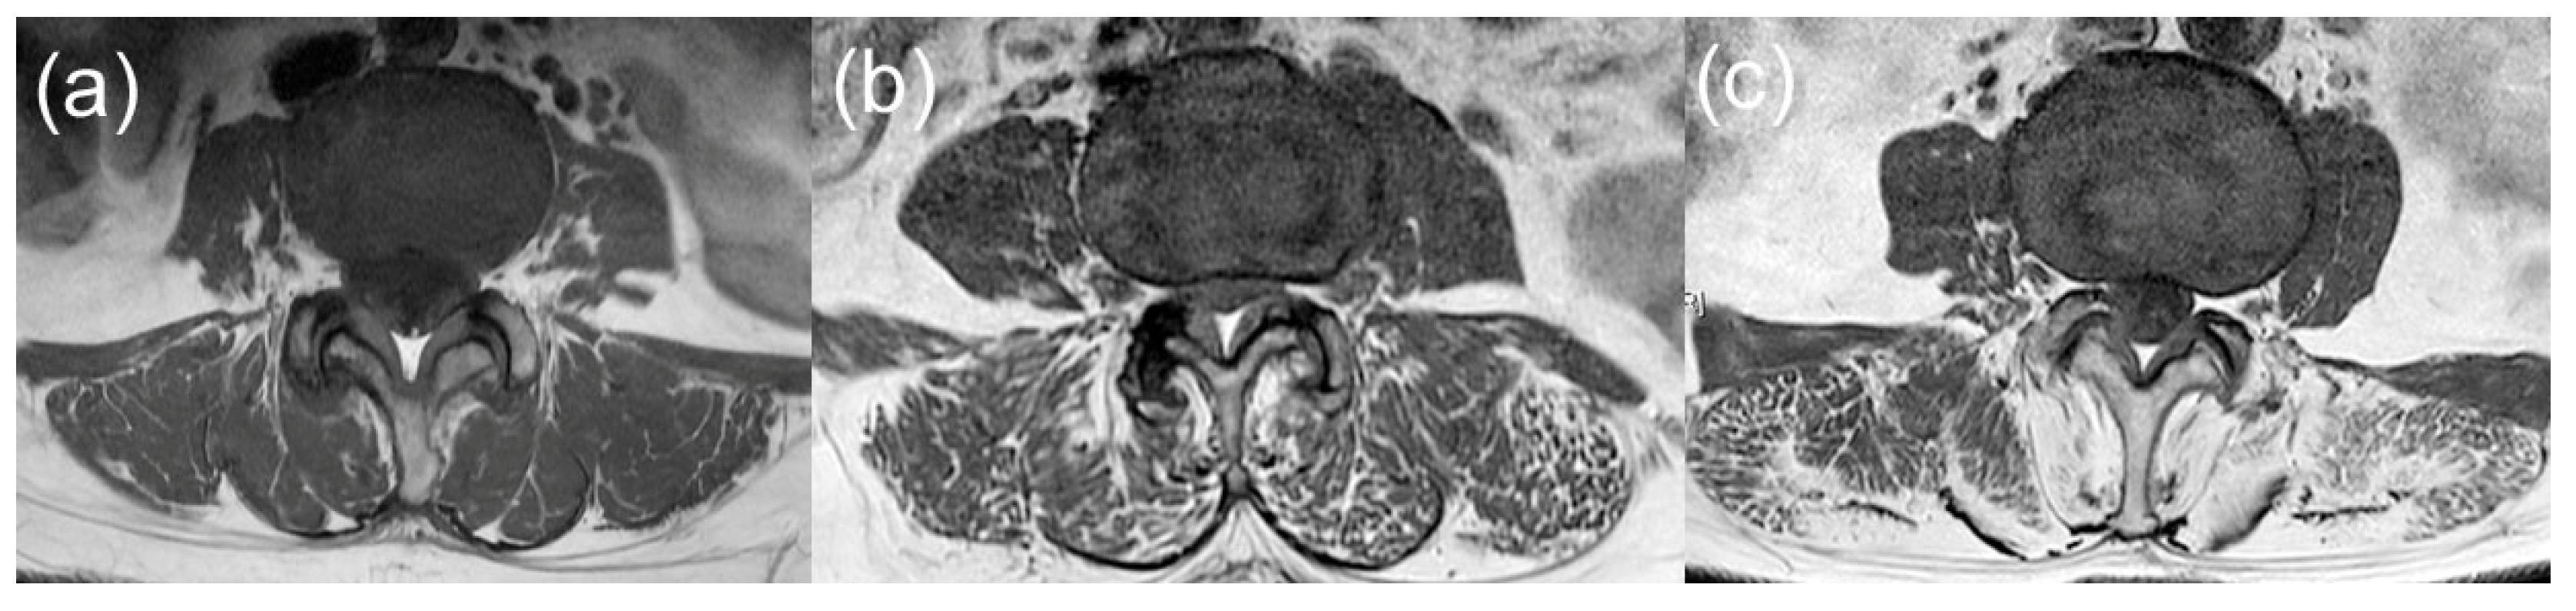

2.3. CSA and Fat Infiltration Measurements